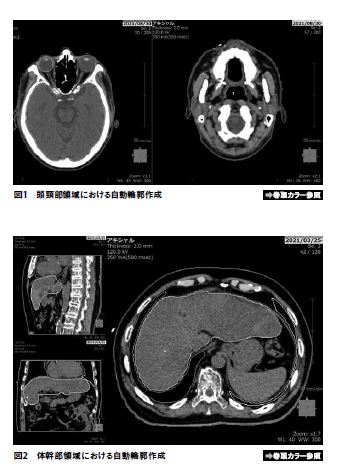

頭頸部、骨盤部領域および体幹部領域について、自動輪郭作成を行なった例を図1~3に示す。また、自動輪郭作成機能を用いて描出した輪郭と、医者により描出された輪郭との一致度(DICE 係数)を表2~4に示す。体幹部領域において、臨床に使用した治療計画に医師による輪郭描出がない場合、もしくは自動輪郭作成が正常に動作しなかった場合(心臓、肝臓で2例ずつ見られた)は評価から除外している。脊髄、直腸、心臓については上縁もしくは下縁の設定に差異があり、視神経は体積が非常に小さくスライス厚などの影響を受けやすいためDICE係数はやや小さい値を示しているものの、その他のリスク臓器については平均値および中央値でおよそ0.8~0.9となっており、高い一致度を示していることがわかる。また直腸に関してはガスが溜まっている場合は自動輪郭の精度はやや悪化するようである。肝臓については体積が大きく輪郭描出にも時間を要するが、自動で輪郭作成ができるような治療計画装置は少ない印象がある。SYNAPSE Radiotherapyは肝臓も良い精度で自動輪郭作成が可能である点は非常に評価が高いと感じる。